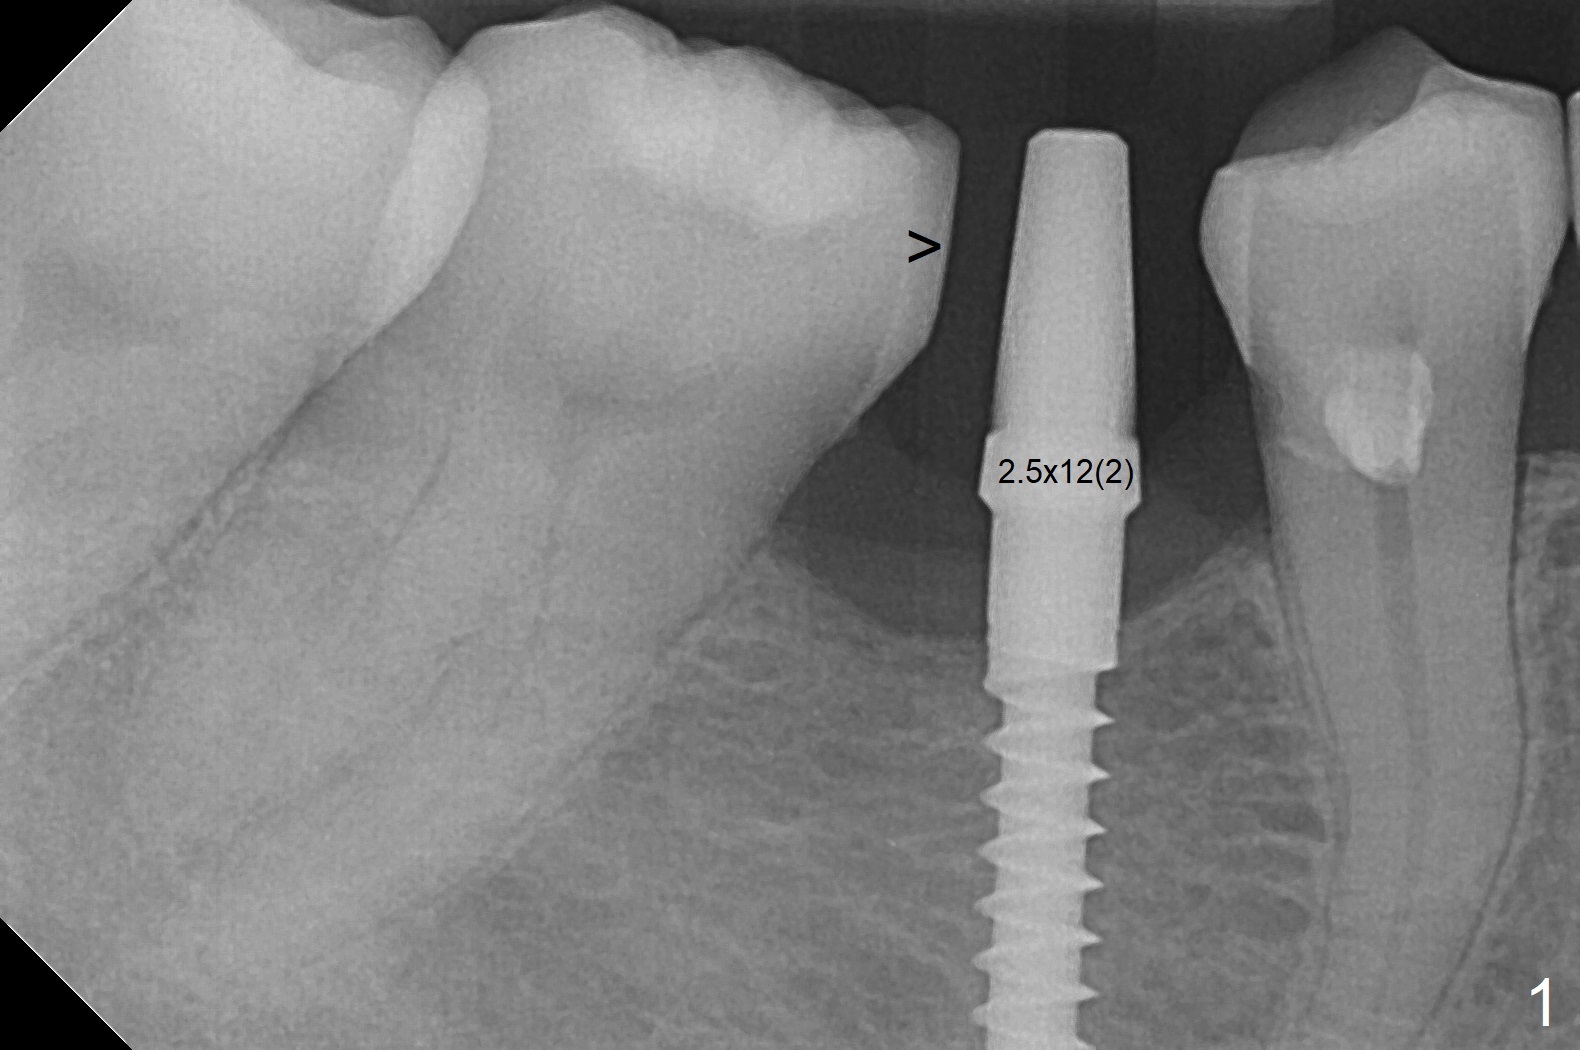

The mesial surface of the tooth #31 is reduced prior to osteotomy (Fig.1 >) so that the mesiodistal width of the edentulous area is 4.5 mm. An incision is made instead of tissue punch because of the narrow keratinized gingiva. The potential osteotomy site happens to have nonkeratinized tissue. When a 2.5x12(2) mm 1-piece implant is placed, it is close to the curved root of the 2nd premolar (Fig.2 *). Because of apparently sufficient clearance from the Inferior Alveolar Canal (Fig.2 red dashed line), the implant is placed ~ 1 mm deeper later. After suturing, periodontal dressing is applied. At patient's request, a provisional is fabricated with occlusal clearance 26 days postop. The occlusal surface of the provisional perforates 3.5 months postop with the provisional having pressed the gingiva, which is consistent with crestal bone loss (Fig.3). There appears no bone loss 3 months post cementation (Fig.4). There is minimal bone loss 11 months post cementation; in fact the bone density around the coronal portion of the implant increases (Fig.5).